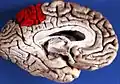

Precuneus of left cerebral hemisphere (shown in red). -

Medial surface of left cerebral hemisphere. (Precuneus visible at top left.) -

Medial surface of left cerebral hemisphere. (Precuneus colored in red.)